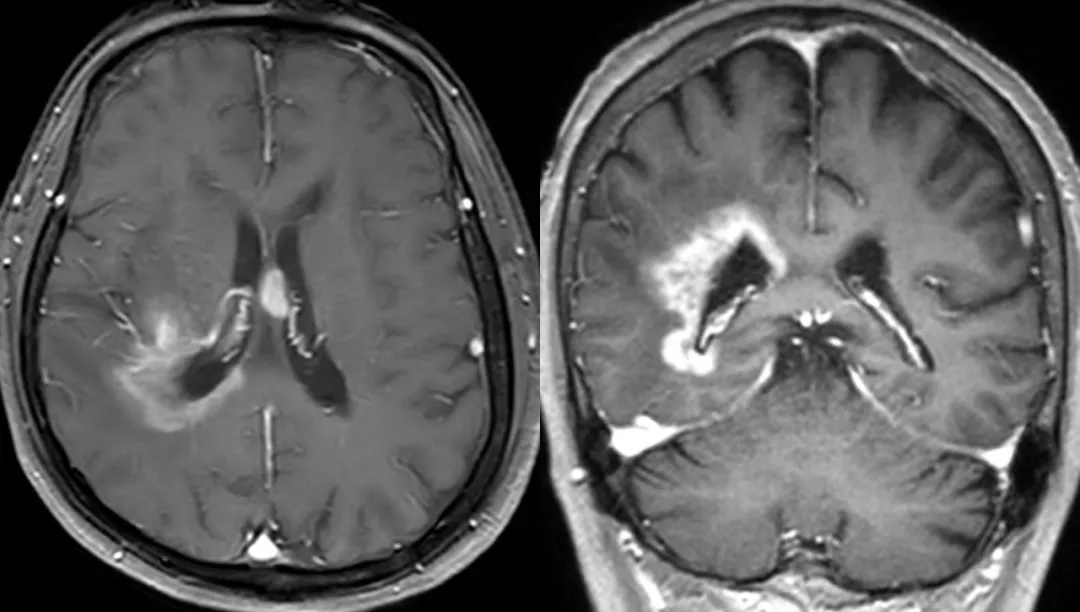

近日,一名80岁老年患者因“头晕伴左下肢感觉减退”就诊于我院神经外科,颅脑增强MR检查提示:右侧脑室后角旁及三角区占位,提示中枢神经系统淋巴瘤或胶质瘤可能。由于诊断不明确,难以提供确切、精准的后续治疗方案。患者高龄,病变位于功能区,多发散在,位置深,直接手术切除创伤大,易导致功能障碍。经术前多学科会诊,决定通过神经外科导航手术机器人辅助下微创活检,明确病理性质,为下一步治疗明确方向。

经过完善的术前准备,我院神经外科主任李峰教授带领团队制定了详细的手术计划,对该患者进行了神经导航机器人辅助下微创脑深部病变活检术,手术历时20分钟,切口直径仅5毫米,颅骨钻取3毫米微小骨孔,术后切口仅缝合一针,安返病房。次日复查颅脑CT未见出血,患者即下床自主活动。病理结果提示“弥漫性大B细胞淋巴瘤”,为患者后续精准治疗提供了保障。

神经导航手术机器人辅助下脑深部病变活检穿刺为微创非直视手术,通过术前将患者颅脑MRI及CT图像数据传输到机器人手术规划系统进行处理,利用图像融合技术,将病变空间解剖位置与各种血管图像精准融合,得到三维立体图像,在规划系统中准确定位病变位置,规划合理穿刺路径,精准避开血管和重要功能区,减少颅内出血等并发症。神经导航机器人定位精度高,穿刺误差小于0.5毫米。不仅克服了传统框架对穿刺路径阻挡的局限性,避免了安装头部框架所带来的痛苦及束缚,而且提高了颅内病变定位的精确度和操作的可视化。